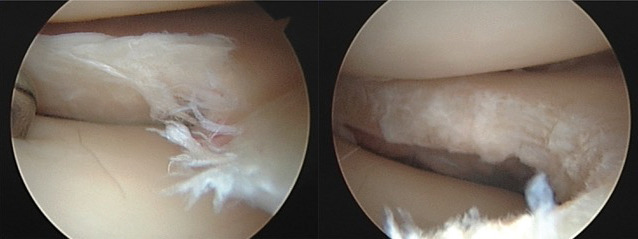

Par opposition au ménisque traumatique, il est question ici de décompensation d’un ménisque-maladie ou de lésion méniscale dégénérative, associée au vieillissement du tissu méniscal. Le ménisque est usé, un clivage horizontal dégénératif en découle (fig. 1), et ce clivage fragilise le ménisque, qui peut alors se casser, se fissurer, sans traumatisme. Il faut se poser la question de l’éventuelle arthrose associée afin de déterminer d’où provient la douleur : du ménisque, du cartilage, des deux ?

La figure 1 montre l’IRM d’une lésion méniscale dégénérative typique du sujet d’âge mûr ; il s’agit d’un exemple de découverte fortuite, le patient étant asymptomatique.